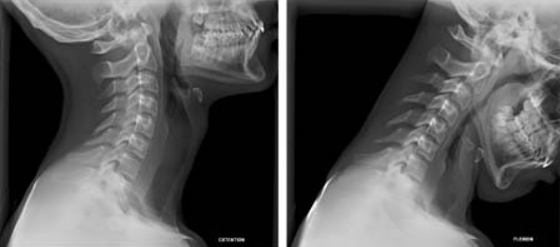

Non esiste una cura definitiva per questa malattia ma diverse modalità per poter attenuare il suo percorso e i suoi sintomi. Prima di tutto, è fondamentale accertarsi che si sia realmente affetti da artrosi cervicale. La prima cosa da fare, in caso di sintomi che possano essere in qualche modo associati a questo disturbo, è sottoporsi ad una visita ortopedica ove, eventualmente, saranno prescritti dal medico esami diagnostici che, attualmente, offrono ancora un grande aiuto per l’individuazione di queste patologie. La radiografia è lo strumento che ha maggior rilevanza in questi casi. Una semplice lastra, infatti, può offrire la possibilità concreta di valutare se siano presenti osteofiti nonché disfunzioni a livello articolare a carico delle vertebre cervicale. Inoltre, grazie alla capacità dello strumento non solo vi è la possibilità di vedere le zone ad alta densità ma anche di valutare la presenza di curve cervicali oppure un’eventuale assottigliamento nella zona compresa tra i corpi vertebrali.